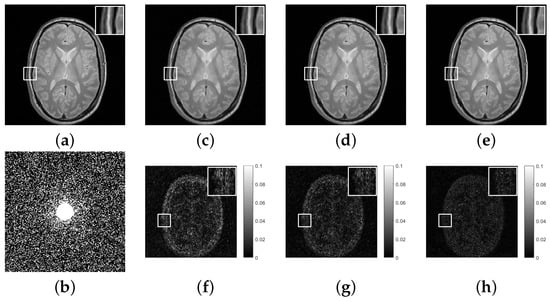

Figure 3. (a), Original image; (b), undersampling template with 30 % sampling rate; (ce), reconstructed images using 1 regularization, 1 / 2 regularization and GMC regularization, respectively; (f), difference between (a) and (c); (g), difference between (a) and (d); (h), difference between (a) and (e).

To further enhance the visual contrast effect, we calculated the difference between the reconstructed image and the original image. Furthermore, we magnified a small portion of the local image to show more details. The reconstruction results of three regularizations are shown in Figure 2, Figure 3 and Figure 4. It can be found that the reconstructed images based on 1 regularization have problems such as blurred edges and residual shadows, and the 1 / 2 regularization reconstruction model also shows similar phenomena. In contrast, the reconstructed images based on GMC sparse regularization are closer to the original images and exhibit higher reconstruction quality.

Additionally, we conducted a quantitative evaluation of the reconstruction results in Table 1. It is obvious that compared with 1 and 1 / 2 regularization, GMC sparse regularization has the best performance in MRI reconstruction and can obtain the lowest RE and highest PSNR.